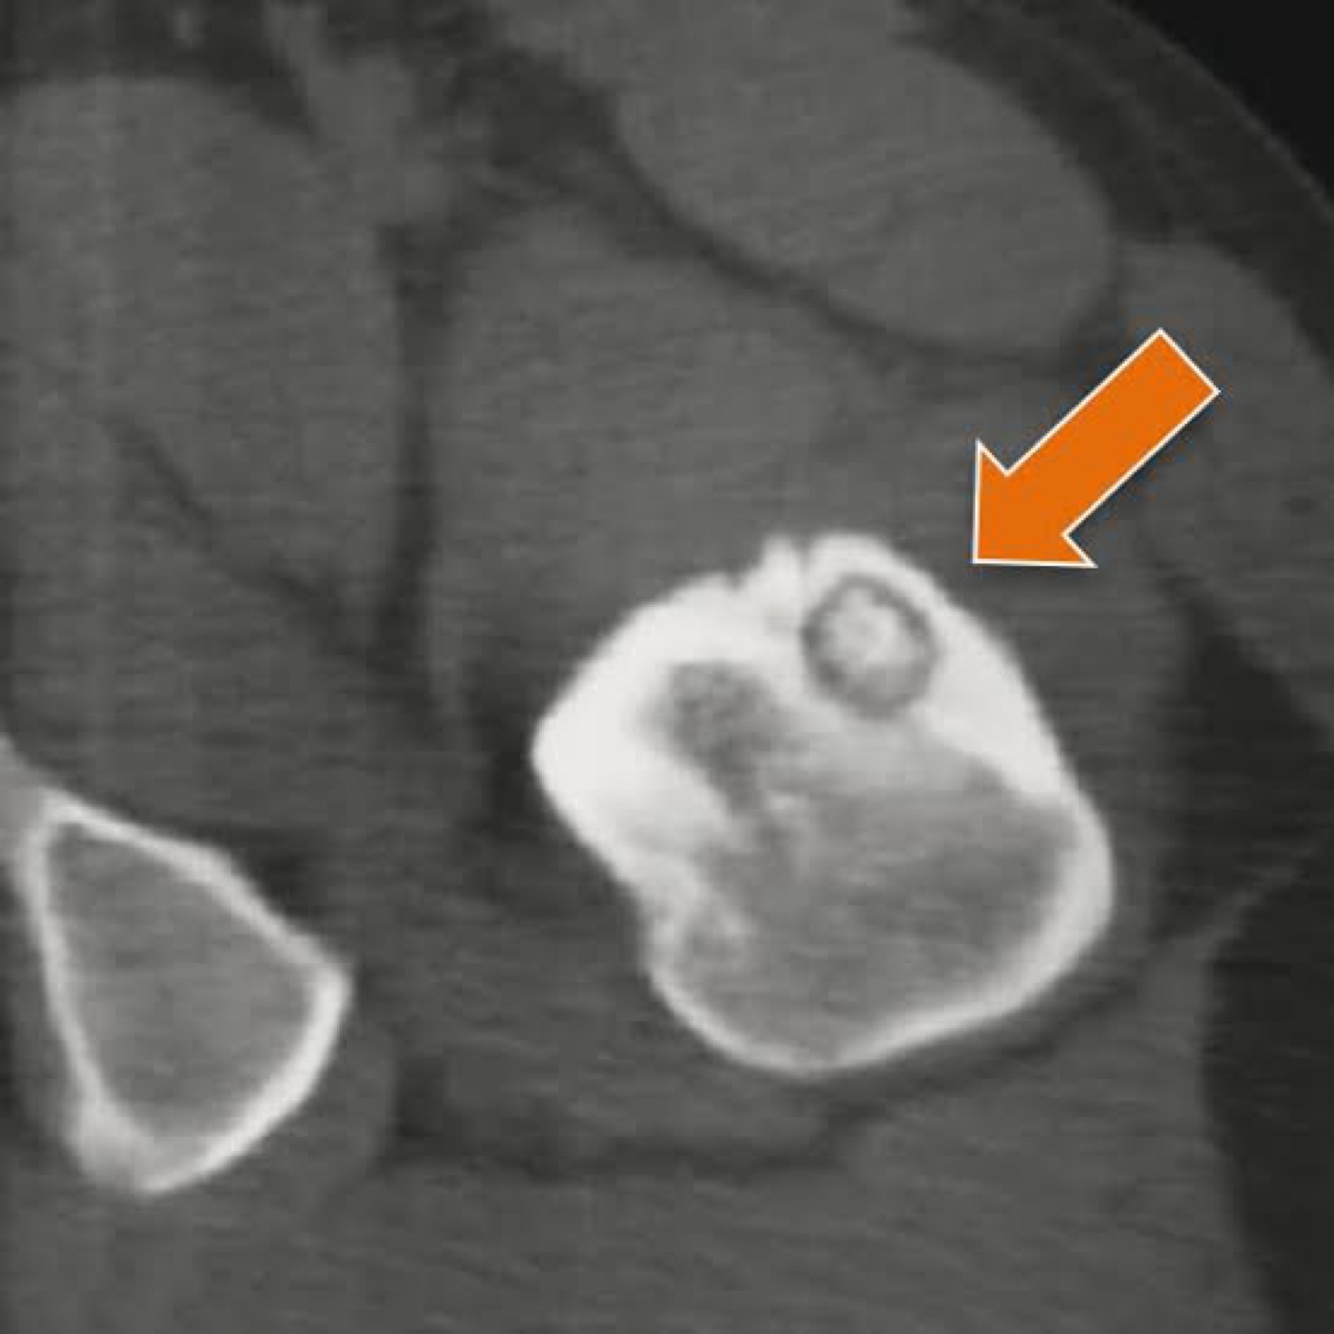

Q

Hipótese ?

A

Condroma periosteal